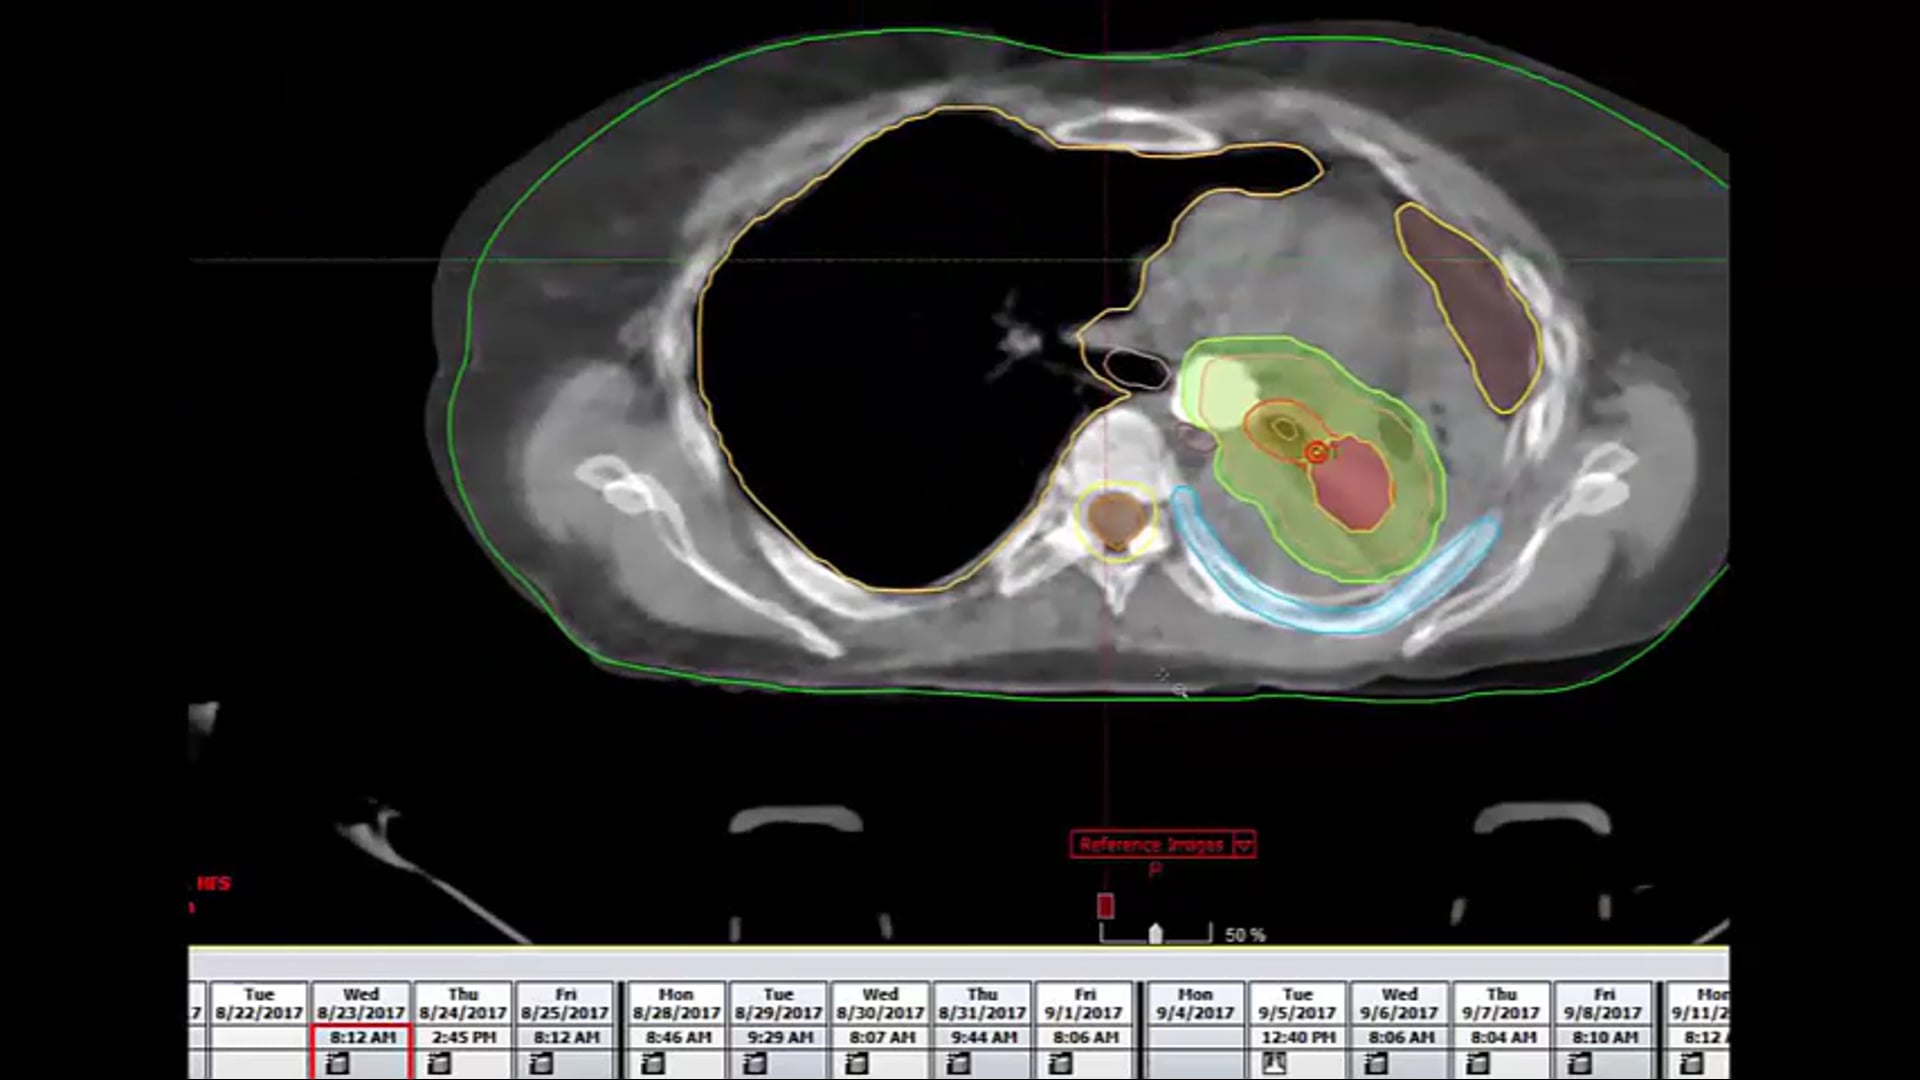

10/06/2022 - Dr. Candice Johnstone - Radiation Oncology - Lung/Esophageal

refused chemotherapy, tumor, dose-volume constraints, CORSAIR, 55Gy 20 regimen, SBRT, CTV, clinical target volume, fractionation